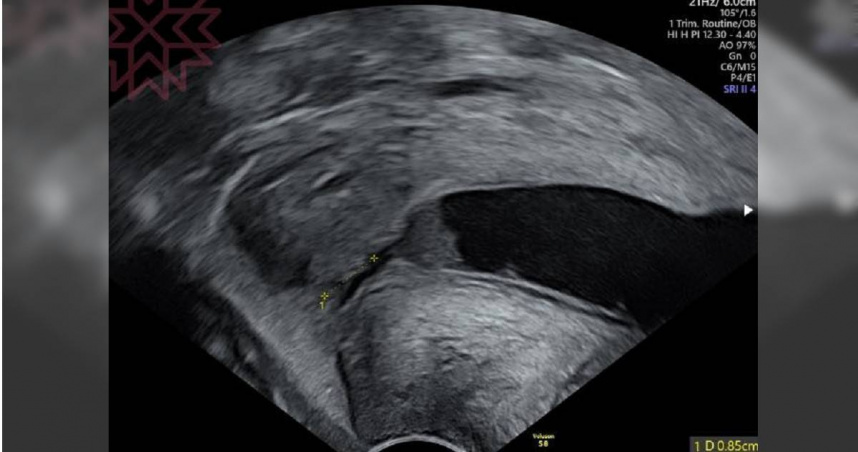

蘇怡寧在其臉書專頁「蘇怡寧醫師愛碎念」發文指出,上週二,一名來自雲林的孕婦特地北上至台中求診,擔憂自己子宮頸長度過短。經超音波檢查後,醫師發現該孕婦的子宮頸僅有0.85公分,遠低於正常值,顯示出明顯的子宮頸閉鎖不全,這一發現讓蘇怡寧直冒冷汗,因為如果不及時手術,可能在一兩週內就會發生破水早產的危險。

一週後,該名孕婦再次回診時,經檢查顯示,子宮頸已恢復至3公分長,且胎兒狀況穩定,醫師預期孕期將能順利進行,這也讓蘇怡寧感慨地說,「看到子宮頸環紮線的位置,感覺這次應該過關了。能讓生命回歸正軌,真的是件令人欣慰的事。」